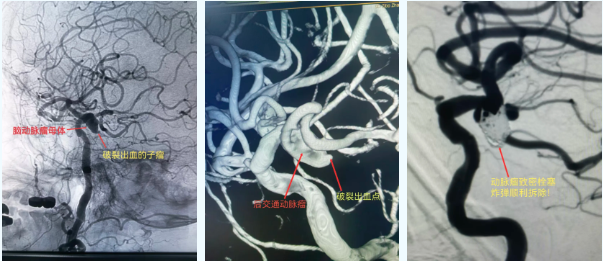

鉴于患者病情危急,卒中中心迅速统筹协调,神经外科专家第一时间开展会诊,结合患者具体病情,当即决定实施介入栓塞手术。随后,患者被快速转运至介入导管室,医护团队默契配合,快速完成全脑血管造影术,进一步明确诊断为右侧后交通动脉动脉瘤破裂。

手术过程中,麻醉科医师全程保驾护航,精准把控患者生命体征,严防血压波动诱发动脉瘤再次破裂;神经外科与介入导管室医护人员密切协作,凭借精湛的诊疗技术,在DSA影像设备的精准引导下,成功为患者实施支架辅助弹簧圈栓塞术,将栓塞材料精准送至动脉瘤部位,顺利封堵破裂口,彻底杜绝了再次出血的可能。术后,在医护人员的精心护理下,患者恢复平稳,顺利清醒拔管,神经功能恢复良好,目前已脱离生命危险,正逐步康复中。